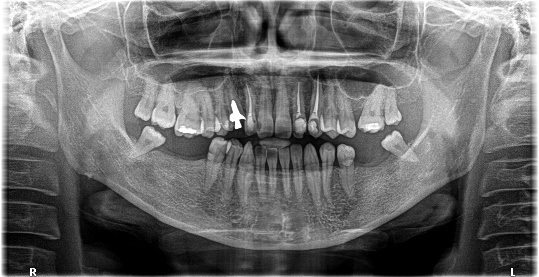

男性Kさん 50代(インプラント)

主訴

歯がグラグラするところ、むし歯のところ、しみるところ、被せ物がとれたところ、歯茎が腫れて血が出るところ、歯が抜けているところがある。すべて治したい。

治療内容

残っている歯を抜歯し、上下インプラント治療をしました。

所感

歯周病が進行している歯、むし歯が進行している歯がほとんどで、レントゲンを撮り、詳しく診てみると、ほとんどの歯を保存することができないことがわかりました。抜歯後は、入れ歯かインプラントの方法があります。治療開始前に患者さんに詳しく現状を説明し、治療法についてじっくり相談しました。自分の歯と同じような感覚で食事できるインプラント治療を選択されました。治療後、表情がとても明るくなり、口元がとても自然で10歳以上若返ったように感じました。「時間はかかりましたが、インプラントにして本当に良かったです!」と素晴らしい笑顔でお話ししてくださいました。

上顎:¥3,280,000(税込)

下顎:¥3,280,000(税込)